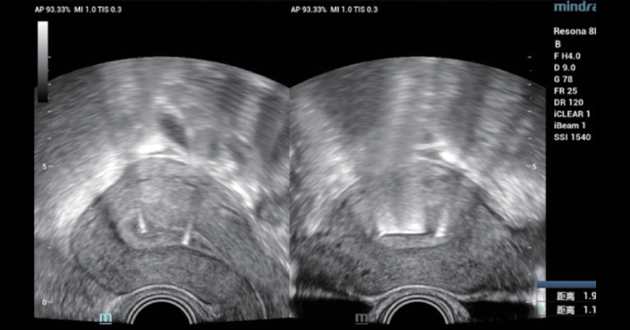

Case 3 - IUD rotation

A 30-year-old female, IUD insertion three months ago, with intermittent abdominal pain and abdominal distention for one month. The 2D ultrasound showed no obvious abnormality, but the 3D ultrasound suggested a rotation of the IUD (Figure 5 and Figure 6). The patient's symptoms were relieved after replacing the IUD.

Figure 5. 2D ultrasound: the distance between the upper edge of IUD and the perimetrium of the uterine fundus was 1.91 cm